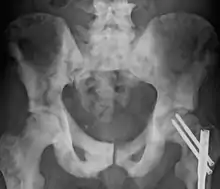

| Sclerosis of the bones of the pelvis due to prostate cancer metastases | |

- Osteogenic bone metastasis caused by carcinoma of prostate and breast